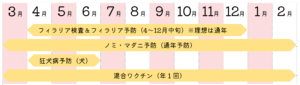

● フィラリア予防(4〜12月)

● ノミ・マダニ予防(通年推奨)

● 狂犬病予防接種(犬)

※フィラリア予防4~12月、ノミ・マダニ予防1~12月をおススメしています